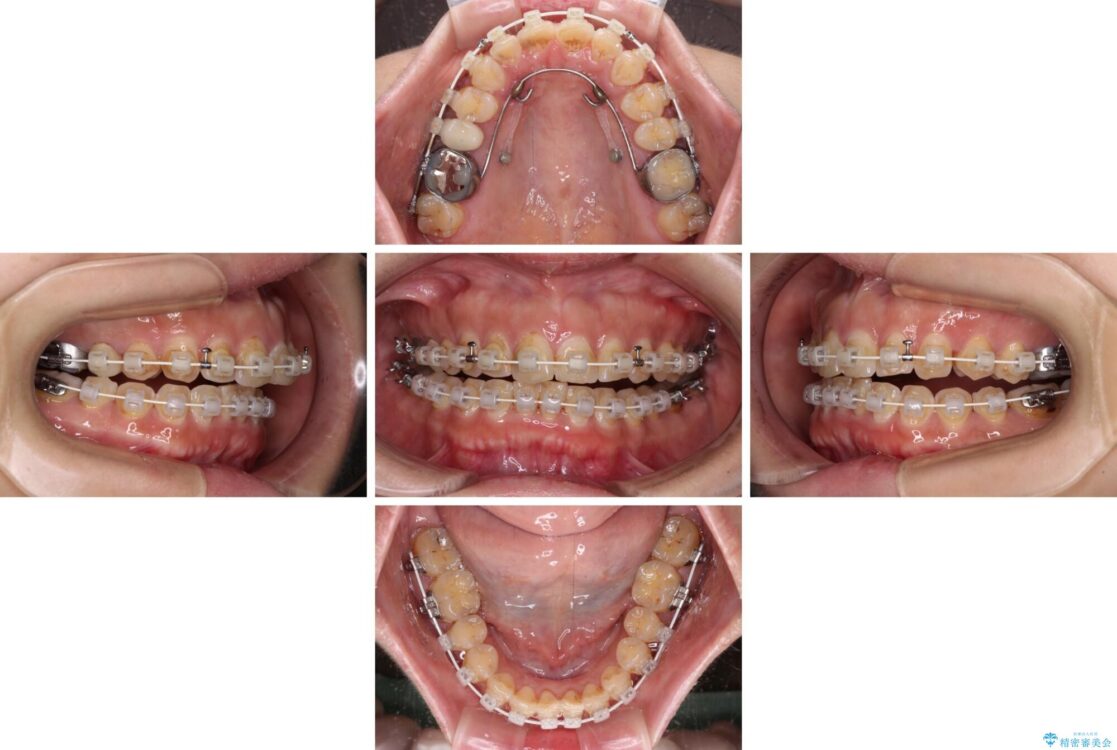

なるべく早めに治療を終えたいとのことで、補助装置を用いて上顎臼歯を後方に移動させ、同時にワイヤー装置にて整えることとしました。

舌の突出癖が原因で上下の歯に大きなスペースが生じていたため、舌のトレーニングをしっかり行っていただくことで、上顎歯列をスムーズに移動させることができました。

治療途中

• 【モニター】飛び出た前歯を整えたい ワイヤー矯正治療 治療途中画像